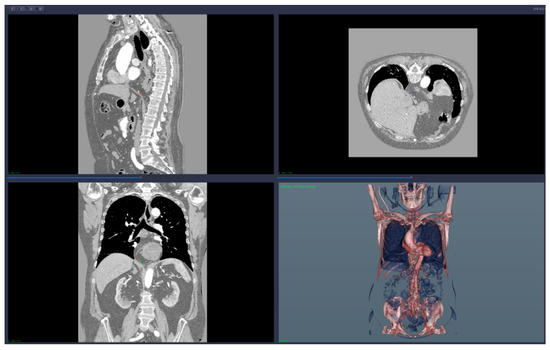

• 3D reconstruction and visualization of arteries (see Figure 1 and Figure 2)

We applied the suggested pre-operatory planning procedure on CT data from a male patient aged 74. The scans were performed using a Siemens Somatom go. Top 128 slice machine [18], with contrast substance (ULTRAVIST 370 I.V.). The series used for planning took 647 slices at a distance of 0.99 mm each. The reconstructed 3D image had 655 × 512 × 647 voxels.

As you can determine from those figures, this particular aneurysm included the whole main part of the superior mesenteric artery, was fusiform in shape and involved all small intestinal branches, which makes the cases difficult to repair.

Figure 1. Images of the 3D CT reconstruction and 2D sections.

Figure 2. Images of the 3D reconstruction of main arteries and mesenteric artery aneurysm.